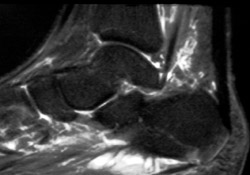

56-year-old diabetic man (A) sagittal STIR image shows edema in the inferior aspect of the calcaneus, consistent with osteomyelitis. (B) Repeat sagittal STIR image six weeks after antibiotic therapy shows normal calcaneus consistent with successful treatement.